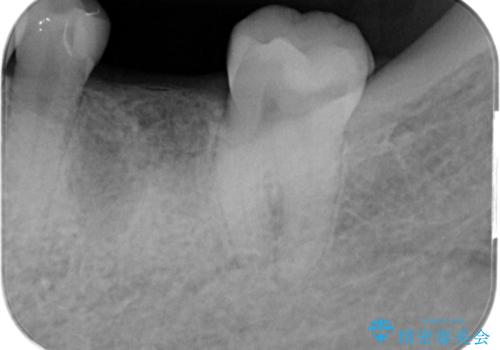

欠損部のインプラント補綴

- 失った奥歯にインプラント治療を受けたい、と希望され来院されました。

前後の歯を削らずに機能回復できるインプラントを用いて審美生、咬合機能の回復を計画します。